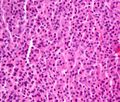

Micrograph showing myeloma cast nephropathy in a kidney biopsy. Hyaline casts are PAS positive (dark pink/red - right of image). Myelomatous casts are PAS negative (pale pink - left of image). PAS stain.

Histopathology